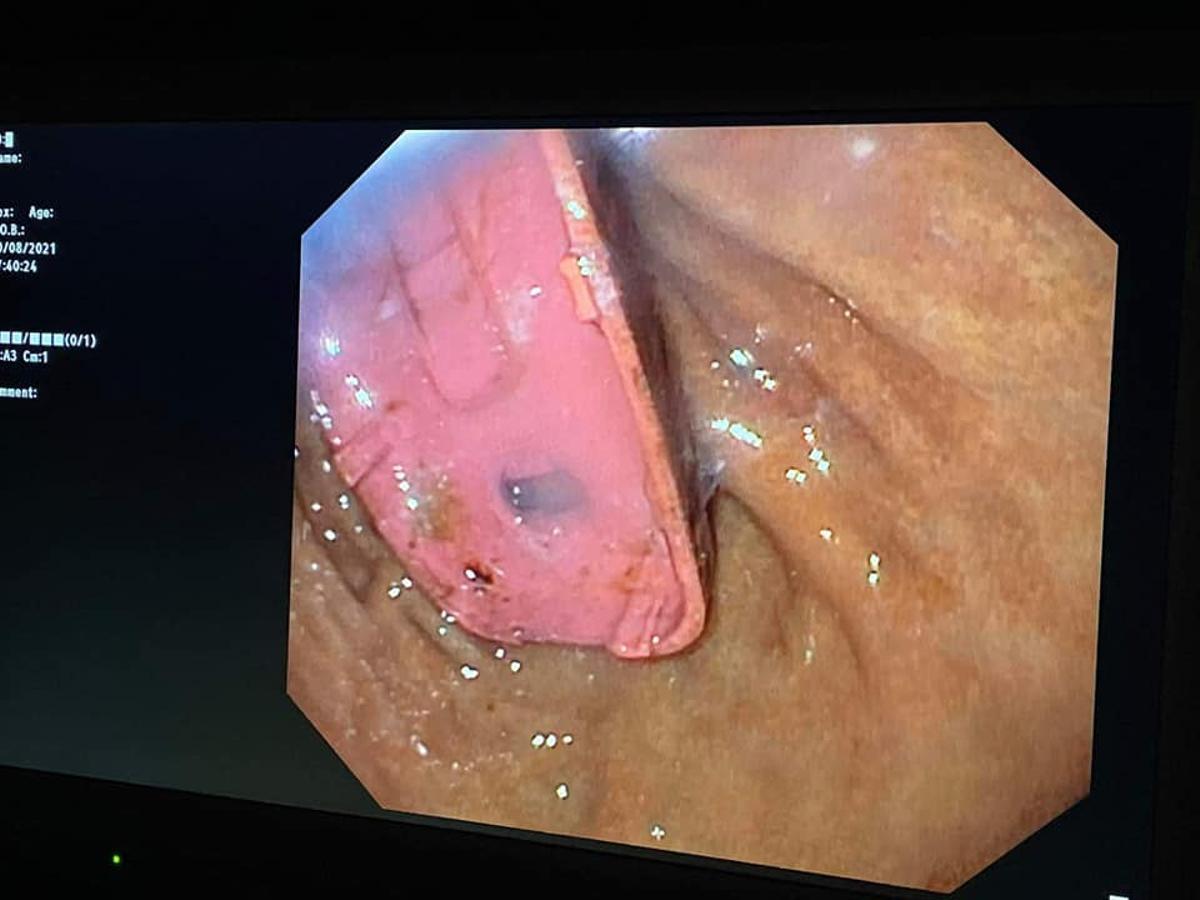

Una imagen del teléfono móvil dentro del estómago del paciente

Contra lo que cabría esperar, no fue necesario abrirle el estómago para extraer el aparato, ya que los cirujanos lograron la proeza de dividirlo en tres partes a través de una endoscopia.

El cirujano jefe que se puso al frente de la delicada operación, Skender Teljaku, ha difundido en Facebook un vídeo y fotografías del proceso de extracción, así como radiografías en las que se observa el viejo modelo de Nokia dentro del estómago. Aviso: las siguientes imágenes pueden herir la sensibilidad de algunos lectores: